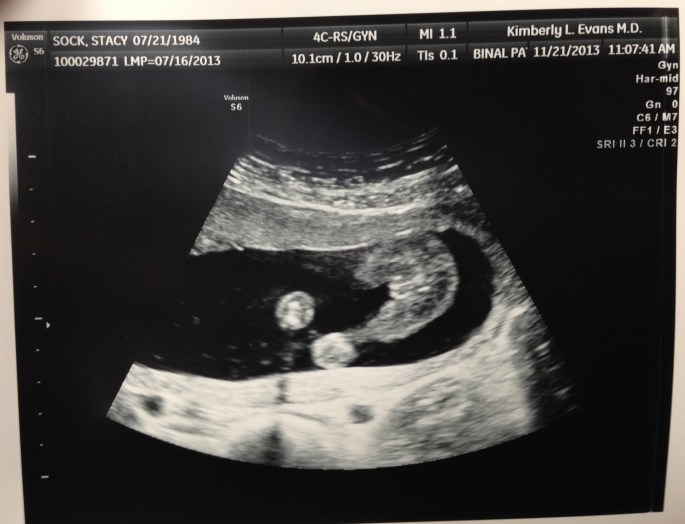

The second the ultrasound tech put the Doppler on my belly, our little sweetheart was showing us her goods. And as he was holding my hand, the ultrasound tech immediately said “girl” just as I whispered it in Bobby’s ear and after those words came out, Bobby gave my hand a little squeeze. Tears came rolling down my face and he got a little choked up. WE’RE GOING TO HAVE A LITTLE GIRL! After the first bout of excitement passed I knew that God had it in for me. I put my mother through so much stress and I can only imagine what I’ve got ahead of myself. I had a good laugh at that thought. I quickly reminded myself how innocent she is.